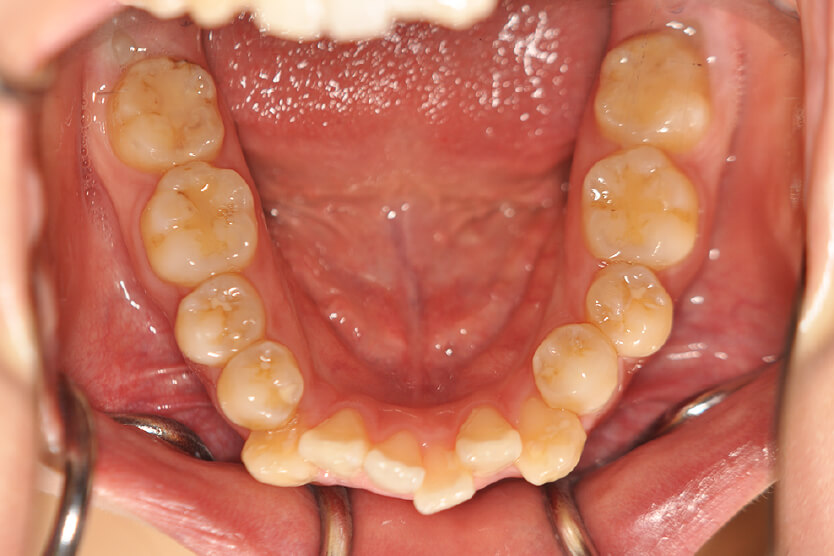

開咬(抜歯)【1979】

初診時

年齢

21歳 性 別 女性

治療内容の詳細 初診時21歳の女性で、出っ歯、下顎前歯部のがたつきを気にされ来院されました。

検査の結果、上顎前突、上下顎前歯部叢生および開咬を伴うアングルⅡ級1類不正咬合と診断しました。

治療としては、上下左右第一小臼歯を抜歯して、セルフライゲーションブラケット装置(デーモンシステム)とマウスピース型矯正装置(インビザライン)で配列を行いました。

この際、上顎に歯科矯正用アンカースクリューを設置し上顎前歯部後退時の土台としました。

開咬については、顎間ゴムの協力もあり改善されました。